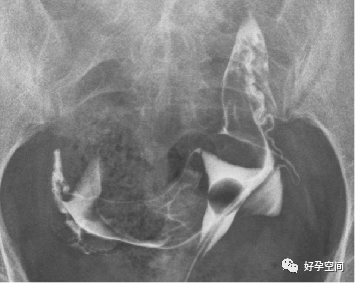

3、骨斑点症

骨盆诸骨均可见多发小圆形高密度影

4、骶髂关节炎

双侧骶髂关节周围骨质密度增高